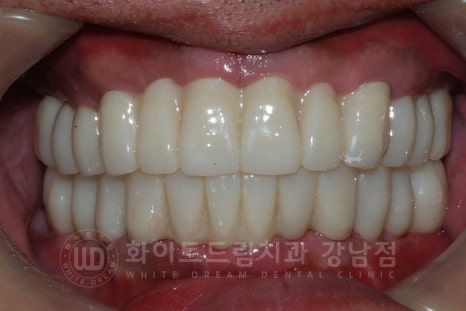

상악 수술 후 약 4개월 정도의 회복 기간을 가진 후 임플란트 인상채득 과정을 거친 후

최종 크라운 세팅을 진행했습니다.

24.01.27 최종 보철 임시 부착

동일 인물이며 동일 환경에서 촬영되었습니다.

치료 기간 : 23.08.12 - 24.03.23

임시 부착 상태로 일상생활을 지내시면서

상/하 교합관계를 확인하면서 불편하신 점은 없는지

새로 생긴 치아에 적응하는 기간을 약 한 달 정도 가지게 됩니다.